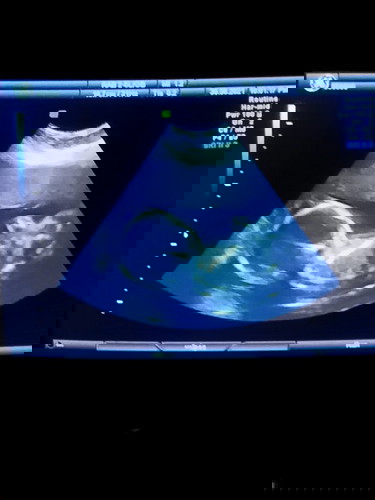

บ้านนี้คุณหมอคาดว่าจะเป็น ผญ ค่ะ แต่ก็ยังไม่ชัด ซาวด์ทีไร คว่ำโชว์ตลอดเลยค่ะ แกงทั้งแม่และหมอ 🤣🤣